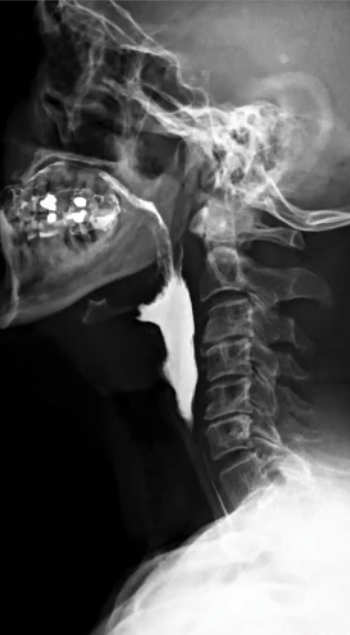

Transit oesophagien et gestro-duodénal (TOGD)

Cet examen permet de visualiser la progression d’un produit opaque au niveau de l’œsophage, de l’estomac et du duodénum et d’étudier les parois digestives.